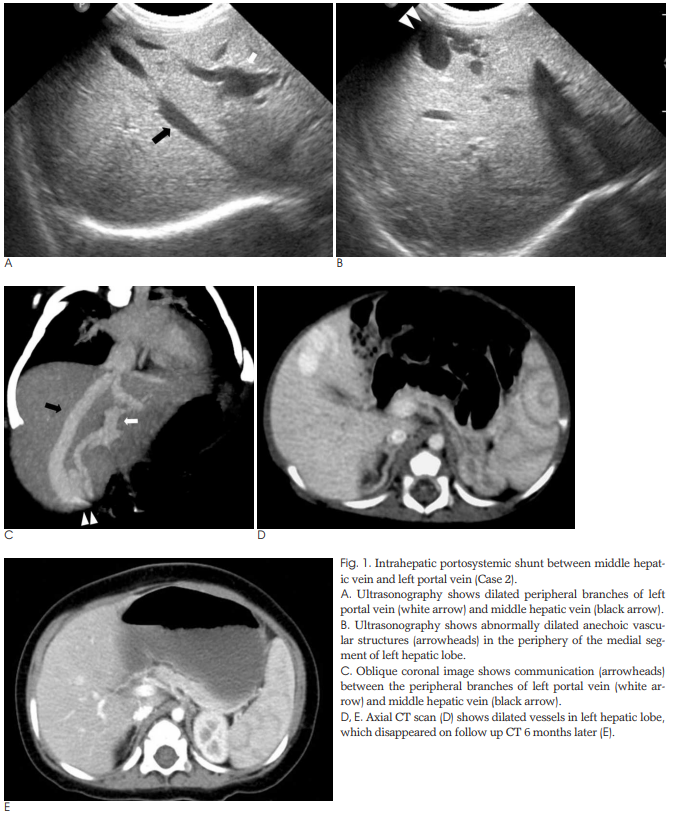

환아 2는 27주 6일, 650 g으로 출생한 미숙아로 산전 초음파에서 심비대, 심막 삼출을 보였으며 생후 지속적으로 직접 빌리루빈이 상승하는 양상을 보였다. 생후 35일째에는 직접 빌리루빈 측정값이 5.6 mg/dL로 상승하여 복부 초음파를 시행하여 간 좌엽의 중간 간정맥과 좌측 문맥 사이 단락으로 진단되었으며, 생후 4개월에 직접 빌리루빈이 0.5 mg/dL로 감소하면서 복부 초음파에서 단락 소실이 확인되었다. 환아 1과 환아 2는 산전 초음파를 시행하지 않았거나 또는 시행 결과 선천성 간내 문맥 전신성 단락으로 의심되는 소견을 보이지 않고, 출생 후 발생한 직접 빌리루빈의 상승으로 복부 초음파를 시행하고 ursodeoxycholic acid (UDCA)로 치료하였다.

신생아의 4명은 초음파와 CT를 시행하였으며 성인 환자는 CT만 시행하였다. 5명 모두 좌간엽에 단락을 보였다. 신생아의 4명은 좌간엽의 원위부에 간내 문맥정맥단락이 있었고 이중 3명은 중정맥과 좌문맥(Fig. 1), 1명은 좌정맥과 좌문맥사이에 단락이 있었다. 이들 중 1명은 좌간엽에 다발성의 단락이 보였다(Fig. 2). 증례 5의 성인 환자는 좌문맥과 좌정맥이 직접 연결되는 정맥관이 남아있는 형태의 간내 문맥정맥단락을 보였다(Fig. 3).

단락이 있는 간정맥은 5명 중 3명은 중정맥, 2명은 좌정맥이었다. 간문맥은 모두 좌문맥의 제대부분(umbilical portion)과 연결이 있었다. 신생아의 2명에서만 추적검사를 시행하였는데 증례 1의 환아는 3개월 후 초음파에서 단락이 소실되었고 증례 2의 환아는 6개월 후에 시행한 CT에서 간내 문맥정맥 단락이 자연 소실되었다(Fig. 1E) (Table 2). 이 두 환아는 초기에 황달과 패혈증으로 입원하여 치료받고 치유가 되어 퇴원을 했으며 추적검사를 시행할 당시에는 특별한 문제는 없었다.